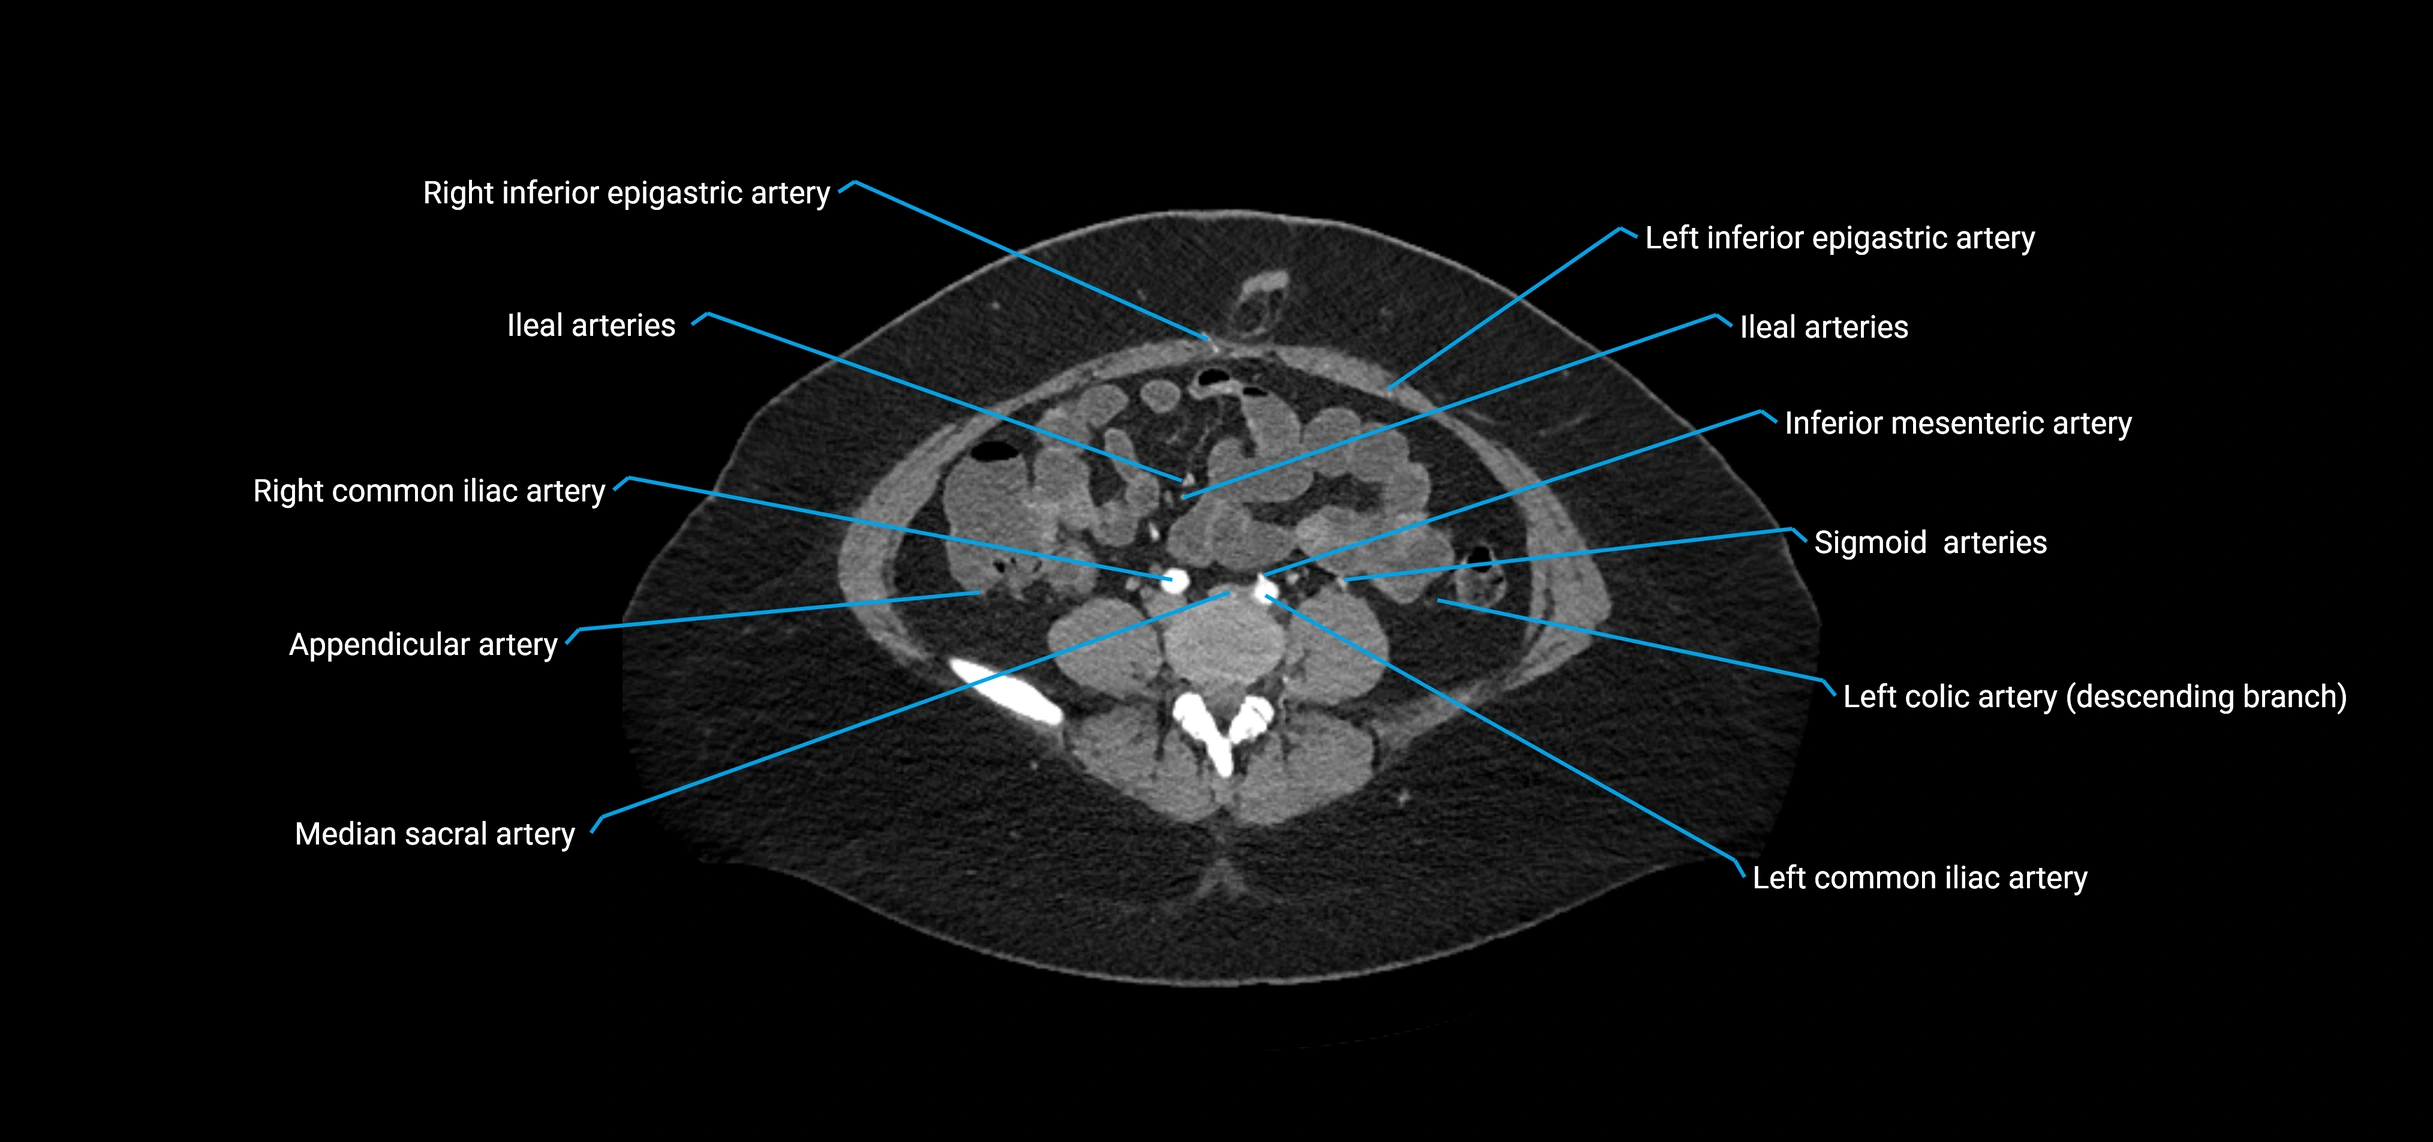

Contrast-enhanced CT (CTA):

• Gold standard for abdominal aortic imaging

• Provides excellent detail of lumen, wall, aneurysm, thrombus, and branch vessels

• Multiplanar and 3D reconstructions help in aneurysm measurement, stent graft planning, and dissection evaluation